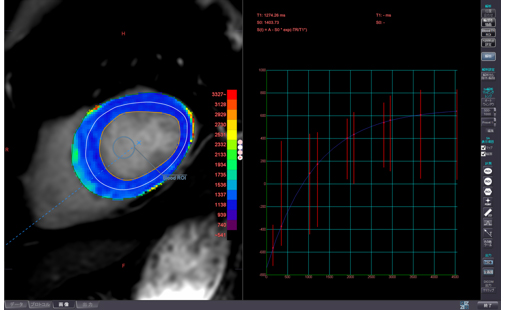

SMILIE

さらに、これまでMRIで評価されてきた心筋性状も、我々の考案する画像処理方法(SMILIE:subtraction myocardial image for late iodine enhancement)によって冠動脈と一緒に評価する事が可能となっています。

Dual energy CT

さらに、これら2台のCT装置にはdual energy システムも搭載しており、体内の物質を弁別する能力があります。特に造影剤の分布を定量的に評価可能なため、各臓器における造影剤の取り込み状況に加えて繊維化の度合いや出血との鑑別等への有用性が期待されます。また、様々なX線エネルギーをシミュレーションした画像も作成できるため、造影剤によるコントラストの向上による造影剤量の低減も可能です。